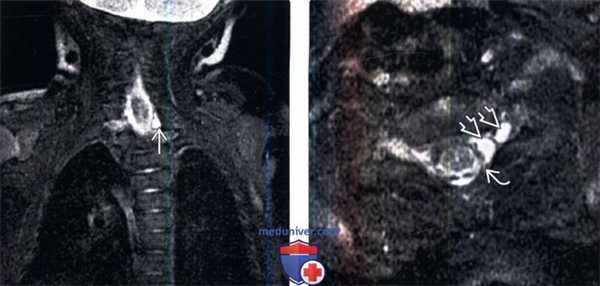

(Слева) На фронтальном FS Т2-ВИ пациента с акушерским тракционным повреждением левого плечевого сплетения и клиникой паралича Клюмпке определяется небольшое псевдоменингоцеле области С8 корешка слева.

(Справа) Аксиальный срез, FS Т2-ВИ, пациент с акушерским тракционным повреждением левого плечевого сплетения и клиникой паралича Клюмпке: признаки экстрадуральной компрессии дурального мешка расположенным здесь псевдоменингоцеле вследствие отрыва корешка спинного мозга и его дуральной воронки.